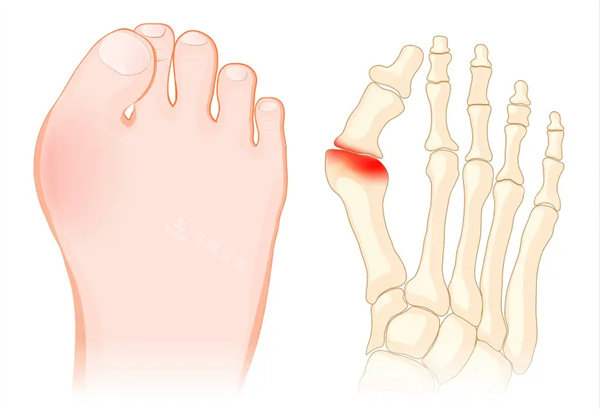

大脚骨图片

大脚骨图示